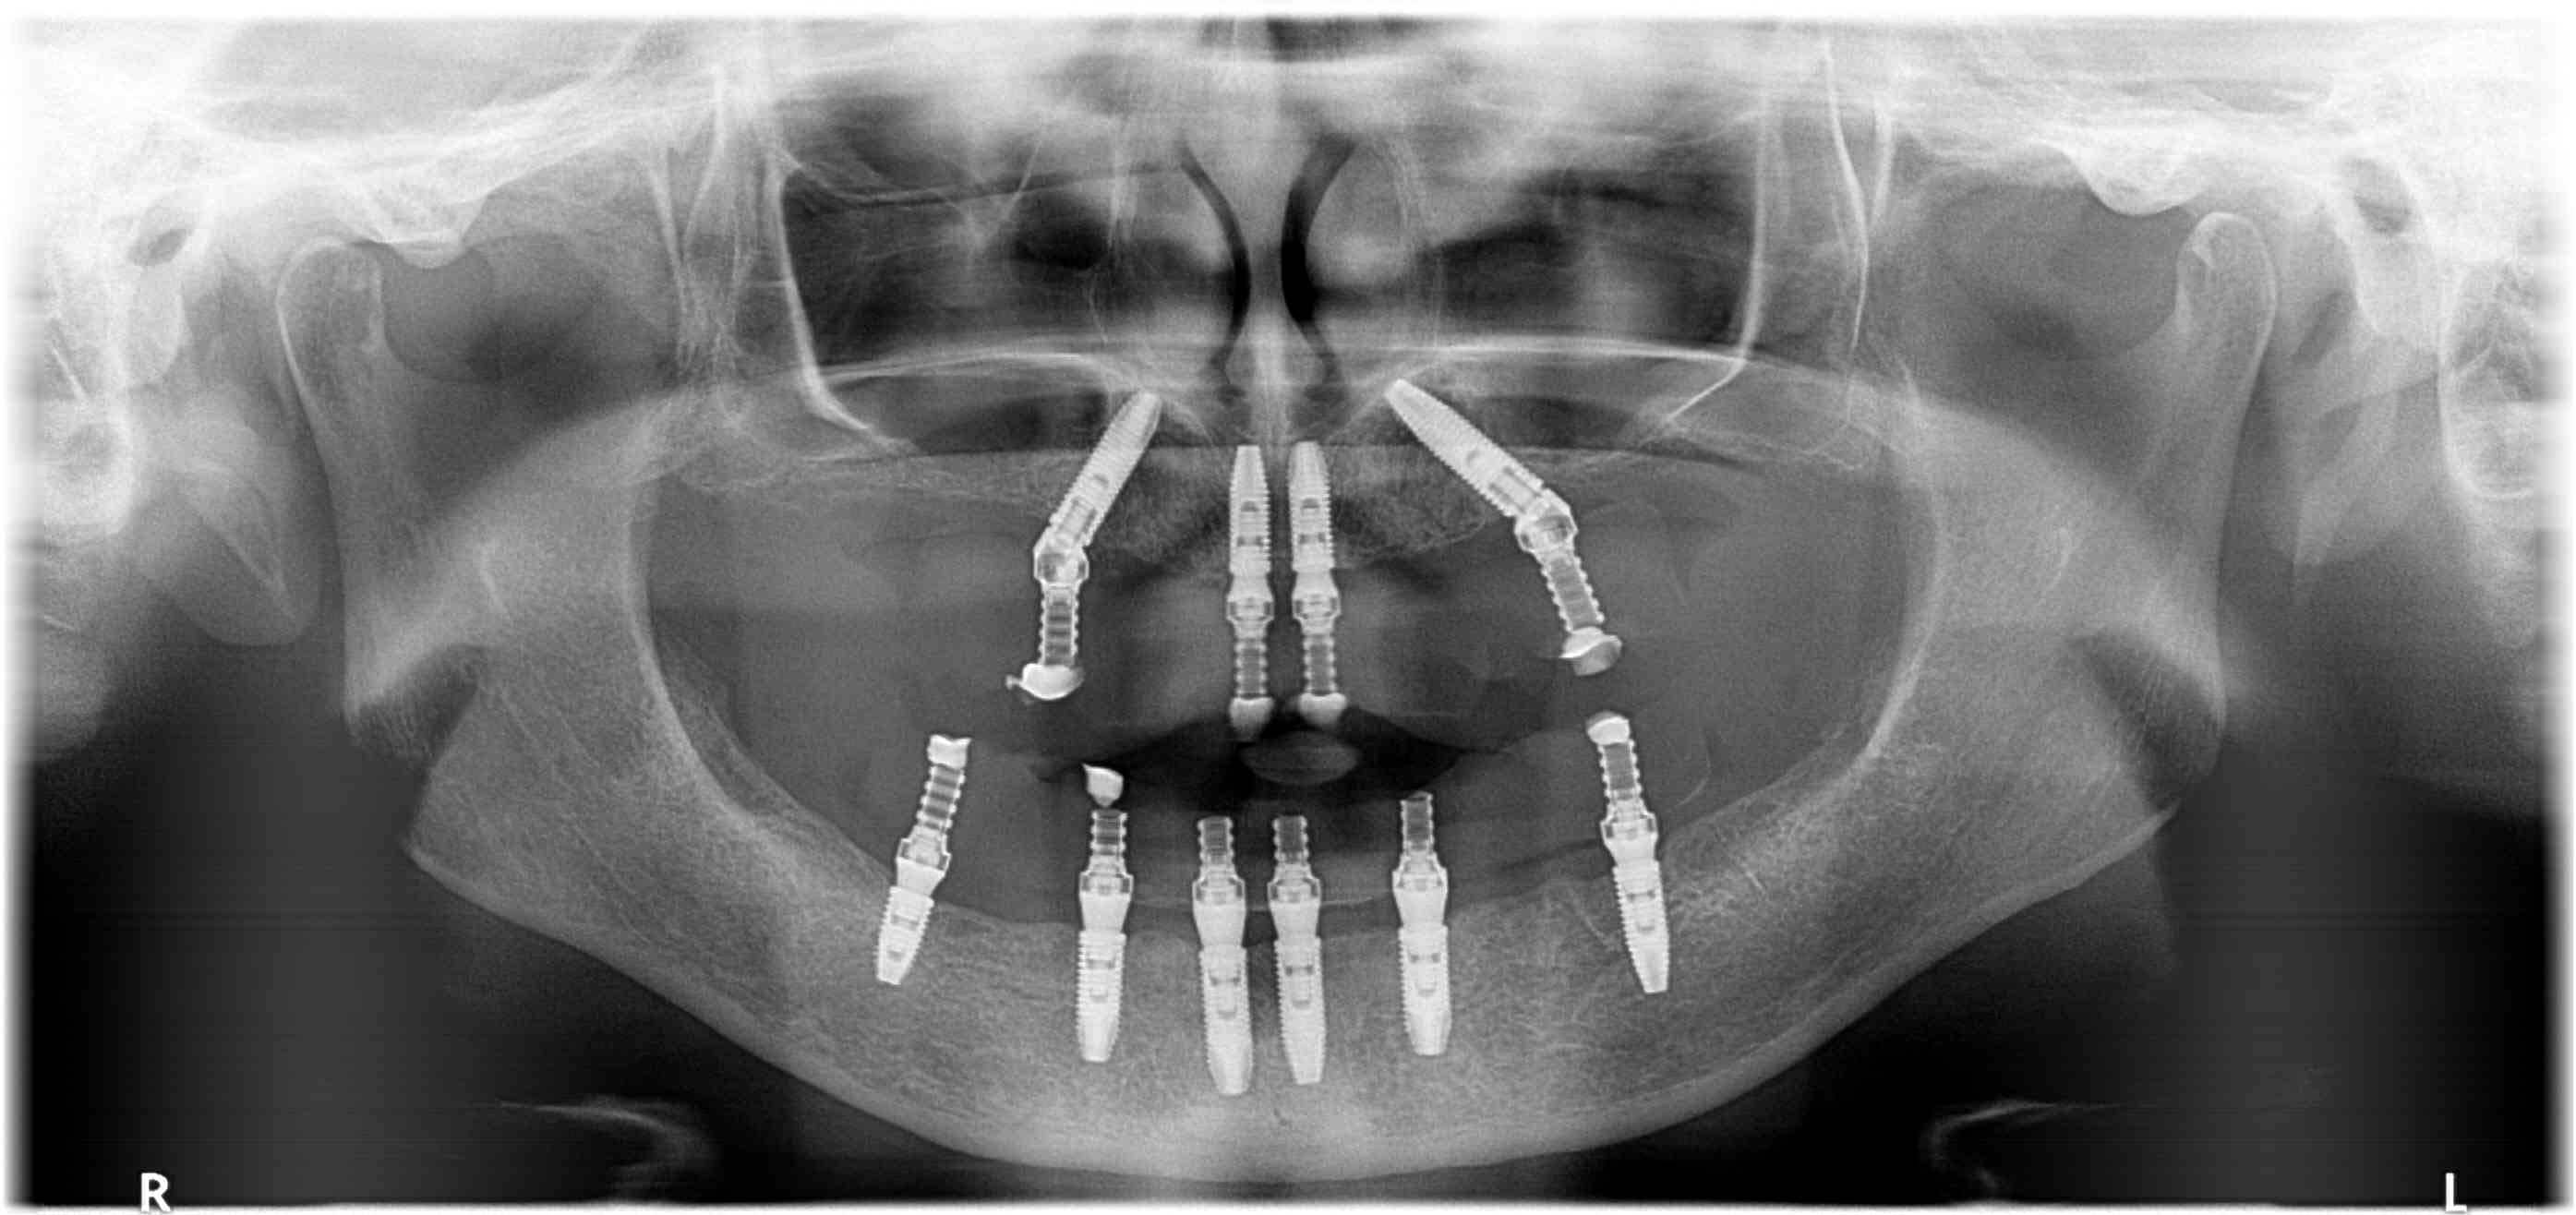

Teljes implantációs fogpótlás kétoldali csontpótlással

A hölgy páciens gracilis csontozata szükségessé tette az implantációt megelőzően a csontpótlást, így kétoldali sinusemelést követően 6 hónap várakozás után került sor az implantátumok beültetésére és az ideiglenes rögzített pótlás elkészítésére.

AllOn4 és AllOn6 implantációs megoldással, halasztott implantációval és azonnali megterheléssel készítettünk rögzített ideiglenes pótlásokat.